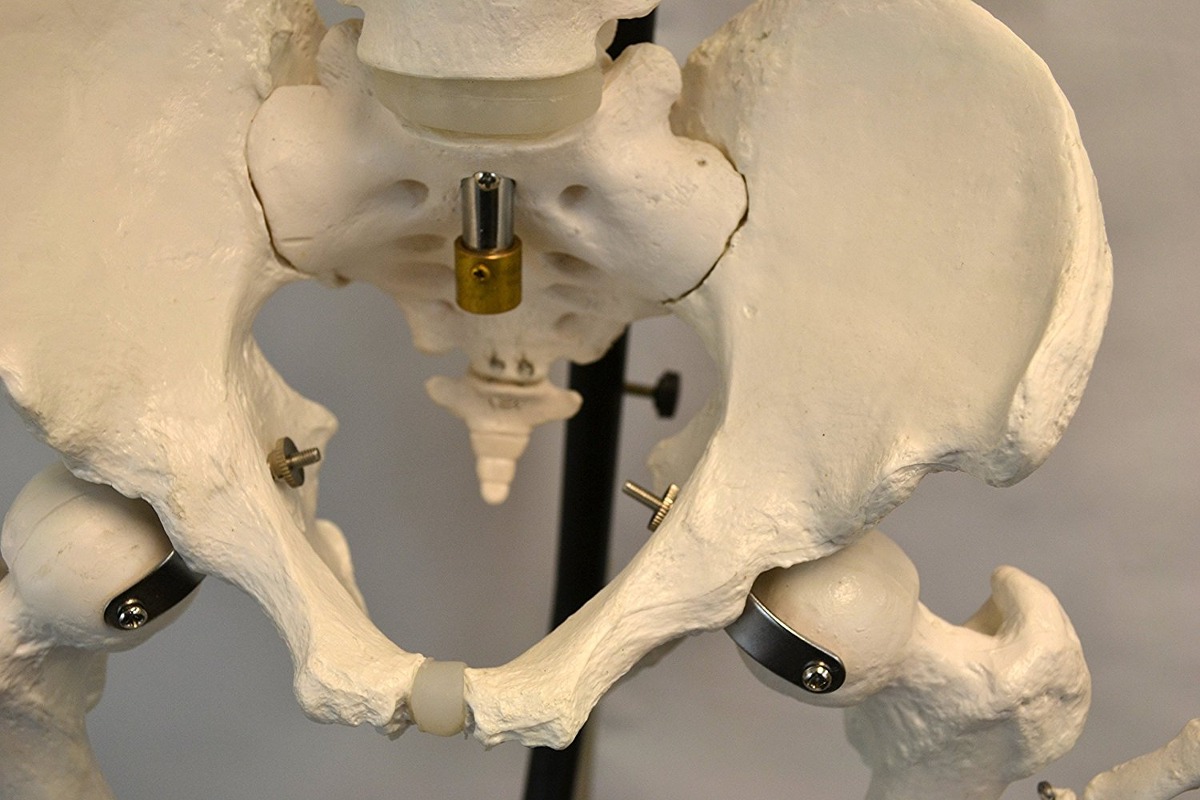

Este modelo es una prima, modelo anatómico calidad médica hecha de un polímero del diseño de plastisol resistente para ser fáciles de limpiar y soportar altas temperaturas. Todos los modelos son pintados a mano por artesanos. Por favor, póngase en contacto con nosotros para obtener más información con respecto a los detalles sobre cualquier modelo. Adicional Filtrado Todos nuestros productos estan en inglés SKU 11111736009

Specification: Esqueleto Humano Modelo Anatómico Con Soporte Colgante, De C

| Weight | 10 kg |

|---|---|

| Dimensions | 60 × 40 × 40 cm |